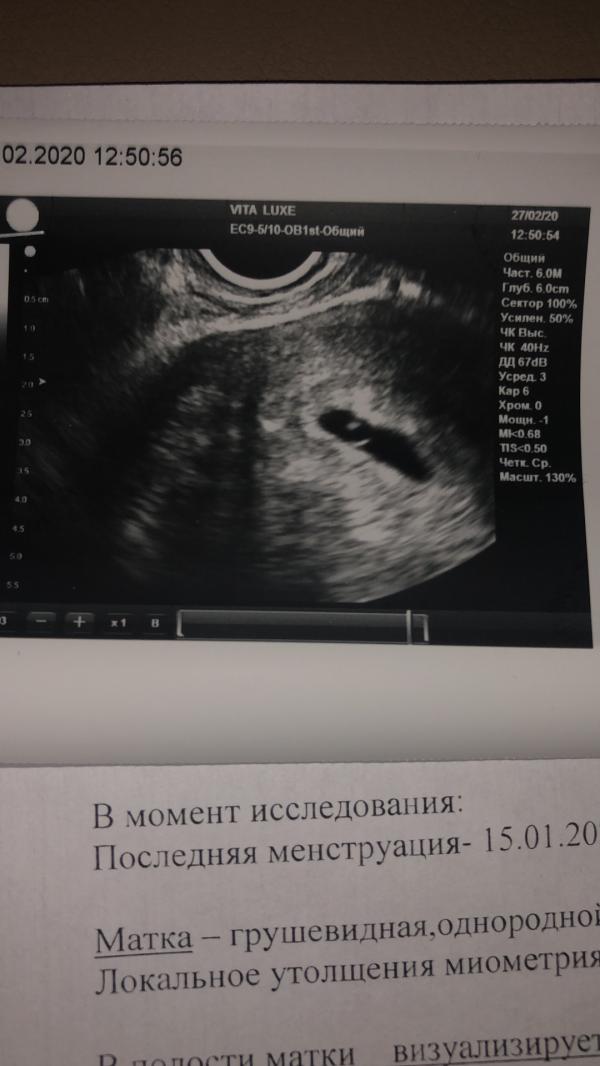

Девочки успокойте меня. Плачу, хотя знаю что нельзя. Ставят угрозу :( узистка успокоила, что не похоже на замёрзшую. Пью утрожестан, лежу.

Вот главное, чтобы сердцебиение появилось . Я за это переживала ,тем более если эмбрион визуализируется .